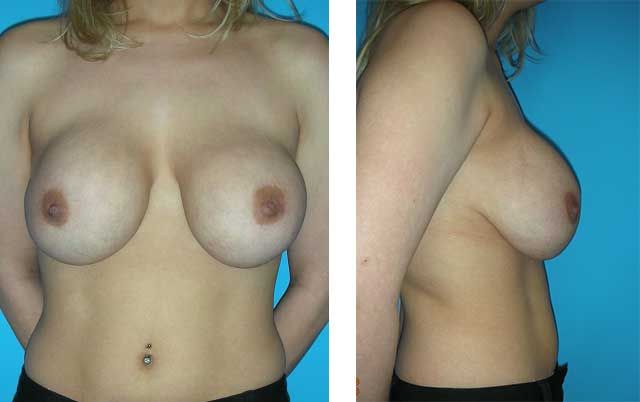

This patient presented to Dr. Agha for corrective breast augmentation. Her primary breast augmentation was performed by a non-plastic surgeon four years ago.

After the second year of her breast augmentation, she returned to her surgeon for implant drooping. According to the patient, the surgeon placed additional saline in her implants during an office procedure.

When presenting to Dr. Agha four years after her primary procedure, the patient had 450 cc saline implants in a subglandular plane, despite weighing only 90 Ibs. Her large saline implants in a subglandular plane had resulted in significant thinning of her breast tissue, skin damage, and stretching of her nipple-areola complex.

The patient underwent a corrective breast augmentation procedure that involved removing her implants, reconstructing her lower inframammary fold, placing silicone implants (275 ccs chosen by the patient) in a submuscular plane, and periareolar mastopexy to remove stretched out skin.